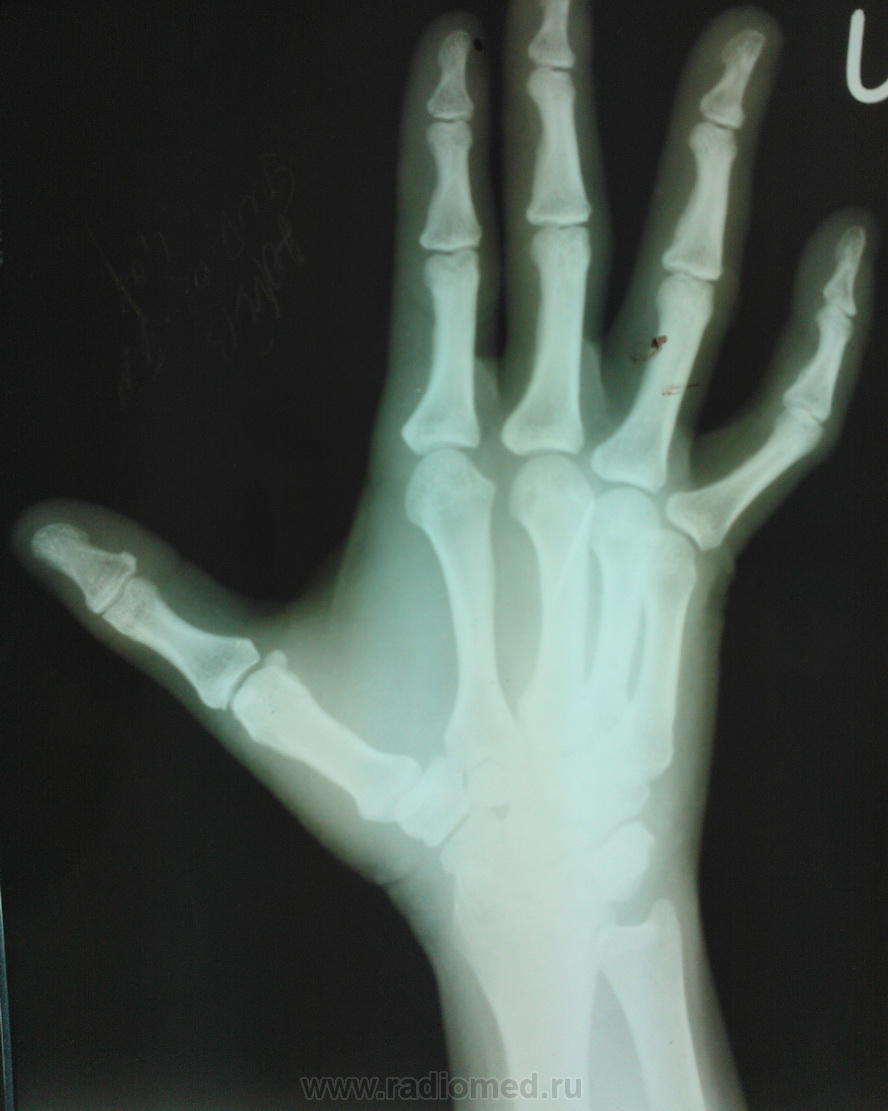

во время стирки одежды игла вонзилась в левую кисть еще весной этого года, с тех пор ее хирурги периодически "наблюдают", один раз амбулаторно пытались извлечь под м\о, не получилось, разок сама съездила в город но там отказали - "такую ерунду могут удалить и ваши хирури", по приезду еще 2 раза в рентген кабинет направляли (наверное подумали что само вышло) и только после этог решили положить в отделение. меня возмутил с каким цинизмом описан анамнез заболевания (фото тоже представлено).  и все это время она ходила страдала с болями в руке, стыдно было смотреть на ее страдальческое лицо сидя в белом халате.

я поэтому то и выложил фото из истории болезни, снимки из тех которые были вложены в историю датировались июнем, июлем, и два раза начало сентября. в начале я написал что игла попала весной этого года. поэтому почти год.